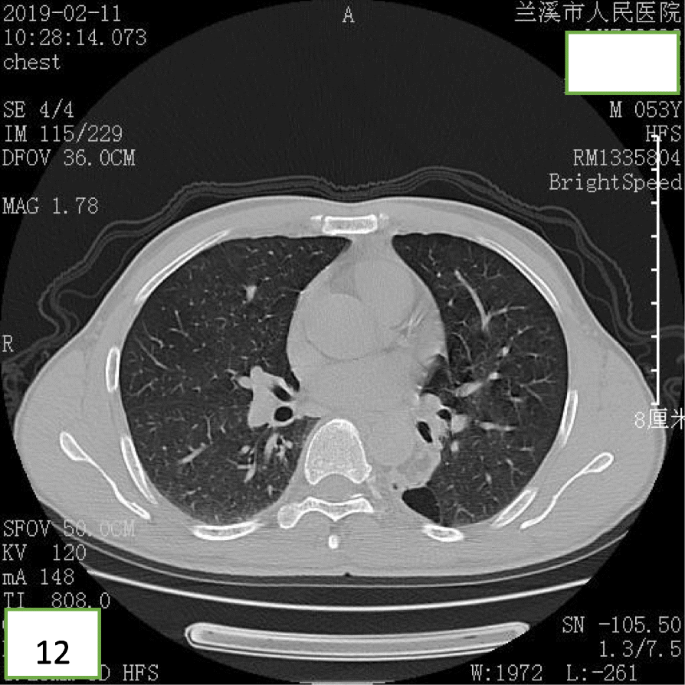

After bronchoscopic intervention, the patient recovered and was discharged. After 18 months of follow-up, the patient was free of symptoms and CT revealed that bronchiectasia remained in the superior segment of the left lower lobe (Figs. 11 and 12), however, no mass lesion was present in the left main bronchus.

At present, a chest CT and bronchoscopy are main approaches to diagnose endobronchial lipoma as the sensitivity of traditional X-ray examination is lower (66%) [14, 15]. The diagnosis can be suggested with fat attenuation on a chest CT and the lack of enhancement after contrast administration [16, 17], because the density of the lipoma is similar to that of normal adipose tissue, and the CT-attenuation value is between − 120 Hu and − 40 Hu. It is helpful to distinguish lipoma from other tumors by accurately measuring the CT-attenuation value of the tumor. In our case, we measured the CT-attenuation value of the neoplasms, which was within the CT-attenuation value range of the lipoma, and helped us make the diagnosis of endobronchial lipoma. In addition, a chest CT can accurately display the shape, size, location, degree of lumen stenosis, the relationship with the bronchial wall, and indirect obstructive signs of a tracheobronchial lipoma [8]. However, it is a challenge to distinguish endobronchial lipoma from bronchial hamartoma by CT, because a bronchial hamartoma is predominantly composed of adipose tissue. Therefore, a bronchoscopy is another important tool for the diagnosis of endobronchial lipoma, can visually show the characteristics of lipoma and biopsy, and can accurately determine the tumor’s location, shape, and degree of blockage of the tumors. In previous reports, it has been suggested that the diagnostic value of a bronchoscopy is very low because of the solid cystic tissue covering the surface of the bronchial lipoma [15]. Only one third of patients can be diagnosed by bronchoscopic biopsy [2]. However, in some studies it was reported that using a cryoprobe, large pieces of the tumor can be extracted, which can help overcome the limitation of a low diagnostic yield [18]. In addition, surgical excision can be performed to obtain pathological diagnosis when neither CT nor bronchoscopy is confirmed. In this case, the chest CT had accurately judged the quantity, size and CT-attenuation value of the tumors, but made an error in judging the location (CT indicated one of the lesions was in the posterior basilar segment of left lower lobe, however the bronchoscopic resection confirmed that the location was in the superior segment of the left lower lobe). These findings display that CT is a reliable method for the diagnosis of endobronchial lipoma even if there are minor faulty judgements. In this case, we failed in diagnosing the tumors by bronchoscopic brushing cytology, however, bronchoscopy was very important to differentiating between benign and malignant tumors since the shape, activity, surface condition, and obstruction degree of the tumors could clearly be observed under the bronchoscope, which provided a basis for the formulation of treatment.